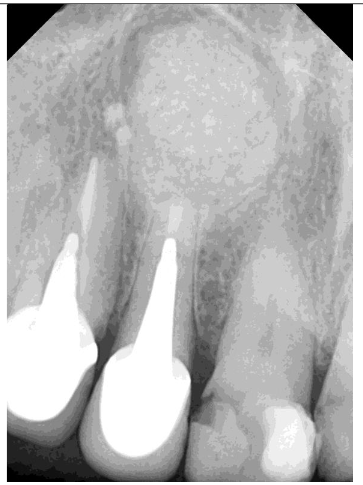

Control x-ray 7 days post-op

The patient experienced moderate discomfort in the first two days post-surgery. Sutures were removed after seven days, and follow-up radiographs showed satisfactory healing. After six months, CBCT scans revealed significant bone remodeling and regeneration of both cortical plates. No symptoms were reported during a two-year follow-up.